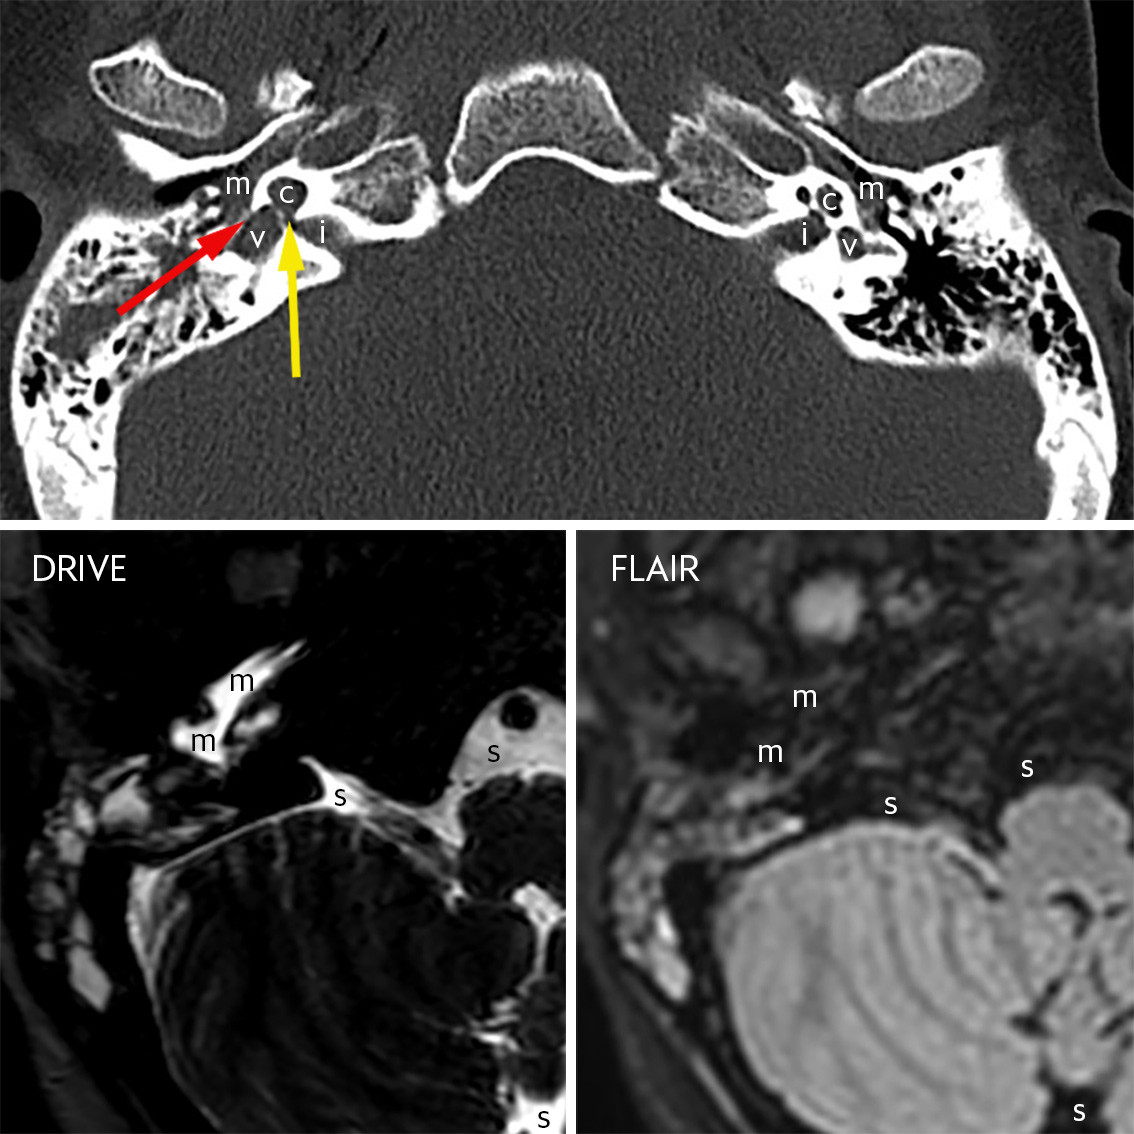

The top image is a slice from a standard head CT scan with volume acquisition, shown here with bone algorithm and bone window at the level of the inner ear. The indication was a critically unwell child with impaired consciousness. The middle ear (m), cochlea (c), vestibule (v) and internal auditory canal (i) are labelled bilaterally. The left inner ear is normal. There is a congenital malformation of the right inner ear. The dimensions of the cochlea are normal, but it has a cystic appearance and is lacking internal architecture. There is a wide communication (yellow arrow) between the base of the cochlea and the internal auditory canal. The vestibule is enlarged, but can be differentiated from the cochlea.

The malformation is consistent with incomplete partition type 1, previously known as cystic cochleovestibular malformation (1). The majority of patients with this malformation have severe neurogenic ipsilateral hearing loss. Some patients will also have leakage of cerebrospinal fluid from the internal auditory canal to the middle ear via a fistula through the inner ear. The image shows material in the right middle ear laterally to the oval window (red arrow). This is a non-specific finding, but it may be cerebrospinal fluid and/or infection, for example.

The two images below are from an MRI scan taken ten days after the CT scan. In the intervening period, the patient had been treated for pneumococcal meningitis. They are slices from two sequences, 3D-T2-DRIVE and fat-suppressed 3D-T2-FLAIR, at the level of the lower part of the middle ear. Only the right side is shown. There is material in the middle ear (m) with a very high signal on the DRIVE sequence and suppressed signal on the FLAIR sequence. The same signal pattern is seen in the cerebrospinal fluid in the subarachnoid space (s) around the brainstem and cerebellum. This is an indication that cerebrospinal fluid is present in the middle ear and is an indirect sign that there may be a cerebrospinal fluid fistula (2). This can be verified with a positive beta-2-transferrin test, provided that sufficient fluid can be collected for analysis (2). A cerebrospinal fluid fistula to the middle ear entails a risk of recurrent bacterial meningitis and can be treated with surgical closure (1).